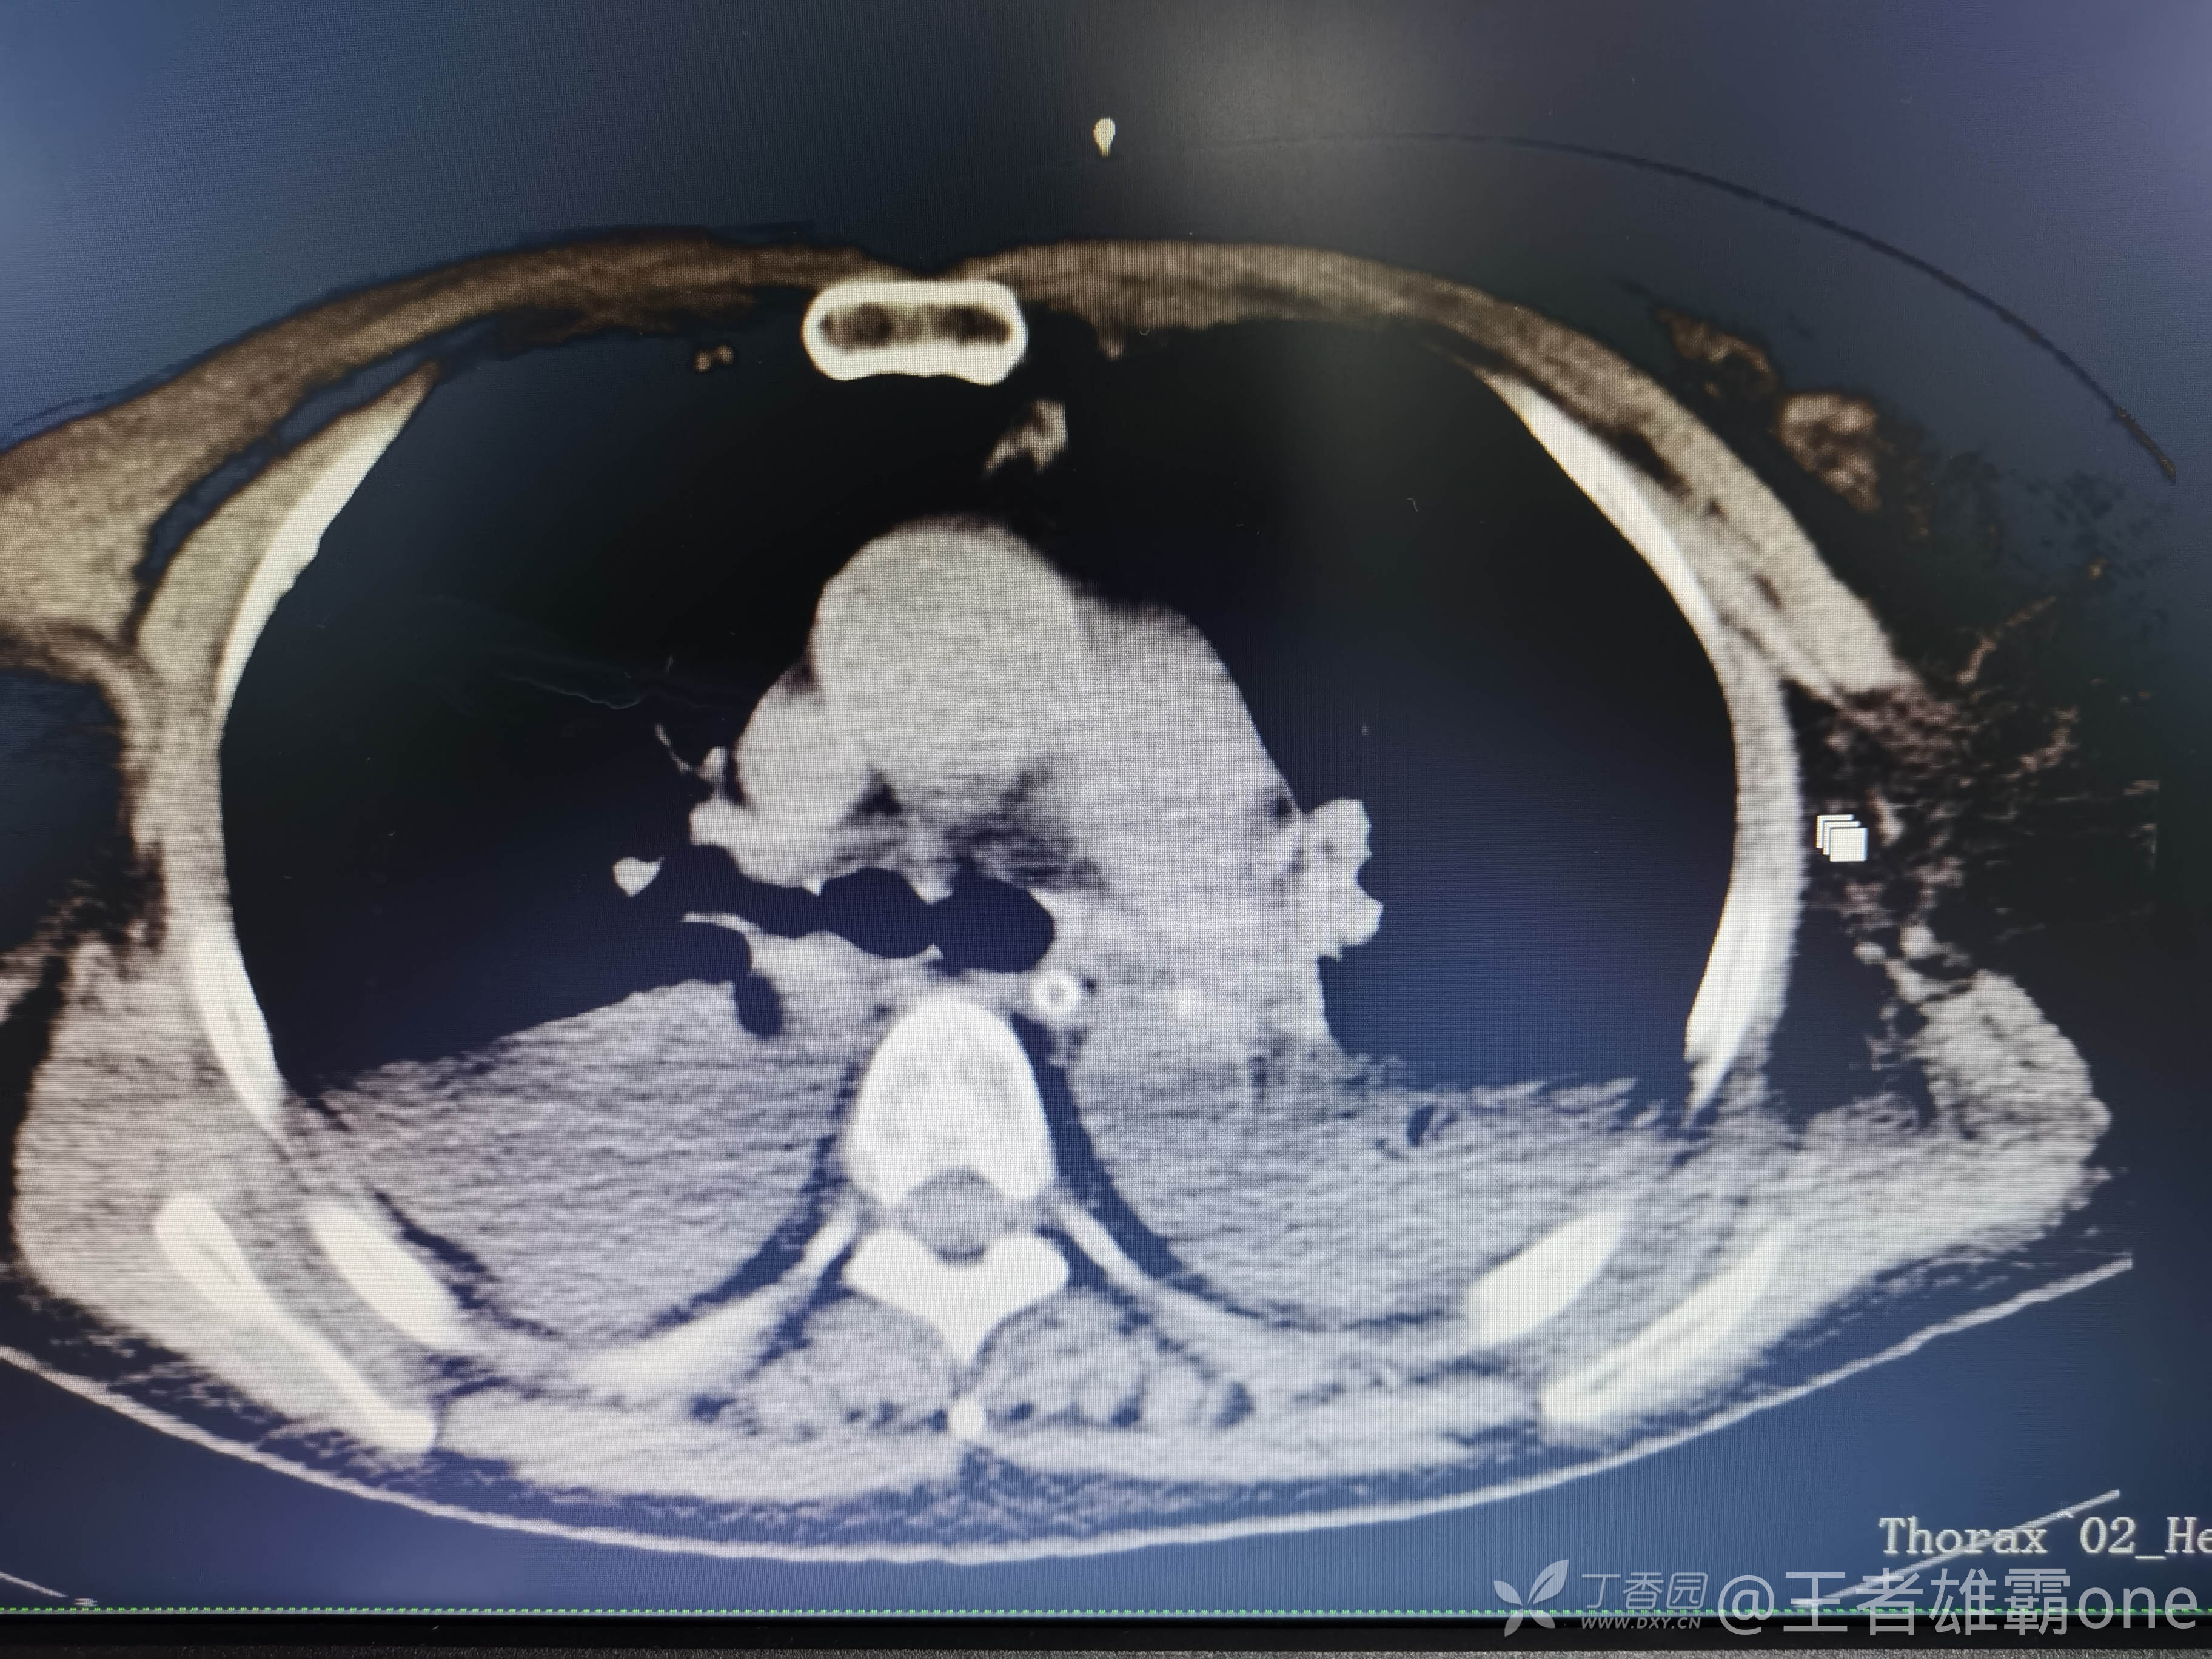

西门开心 推荐63岁女性,因车祸致短暂神志不清、多处疼痛4h入院。简单病史:伤后送至医院急诊就诊。完善头胸腹CT等检查,完善新冠核酸、血常规等化验。血常规提示血红蛋白62g/L。头颅CT提示未见明显外伤性改变。胸腹部CT视频见下:

早上复查血常规:血红蛋白100g/L,白细胞11.1×109/L,血小板29×109/L。凝血功能:APTT37.9s,纤维蛋白原3.01g/L,凝血酶时间18.6s,D二聚体21530ug/L。生化:白蛋白36.2g/L,胆红素指标正常,谷丙56U/L,总胆红素38mmol/L,直接胆红素12.1mmol/L,谷草57U/L,肌酐91.1ummol/L,尿素13.97mmol/L,超敏C反应蛋白142.1mg/L。降钙素原17.70ng/ml。脑钠肽前体2164pg/ml。复查胸部CT: